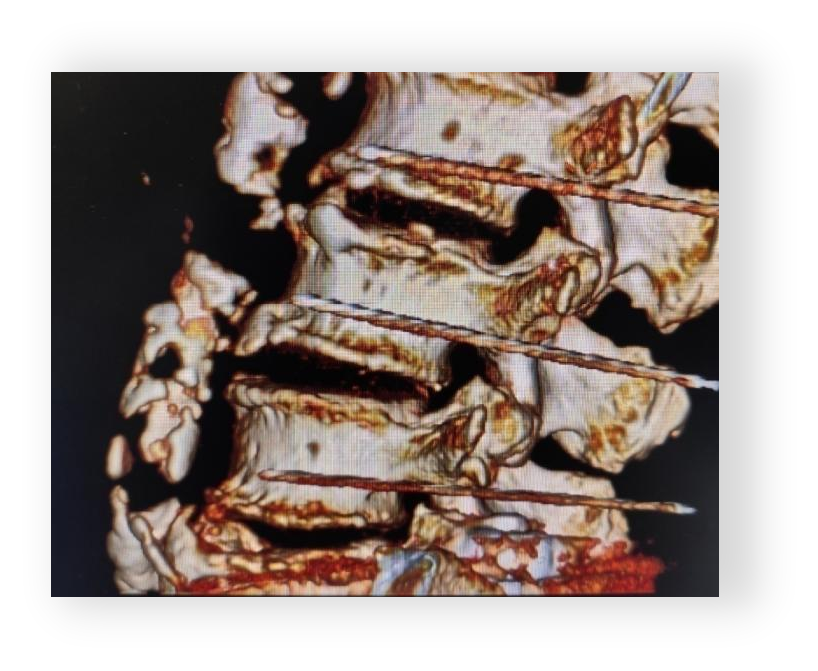

♦ 精准定位:CT三维重建结合体表解剖标记,规划腰2-3交感神经节靶点。

2. 手术过程

♦ 麻醉与入路:局麻下采用俯卧位,CT引导经皮穿刺至腰2-3交感神经节,射频电极到位后行感觉及运动测试(50Hz/2Hz),确认无运动神经受累。

♦ 关键步骤:

射频参数:80℃射频热凝,持续90秒,消融异常兴奋交感神经纤维。

即时效果:术中患者自述下肢温热感,疼痛减轻50%。

术中安全:全程生命体征监测,无出血及神经损伤。

术中影像: